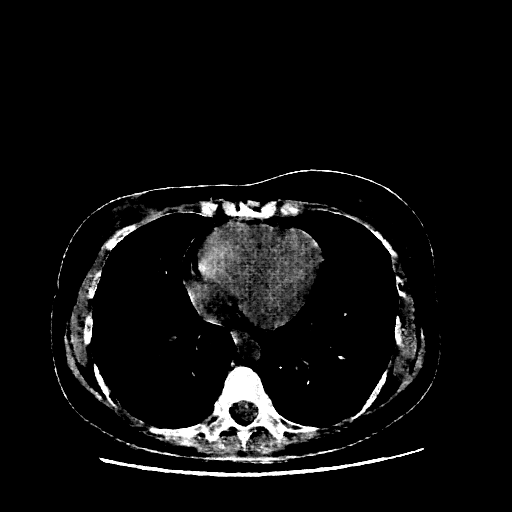

Generated VENOUS CT scan (A→B translation)

Mediastinum window (WL 40, WW 400 β†’ Low βˆ’160, High +240)

Actual HU range: [-160.0, 240.0]